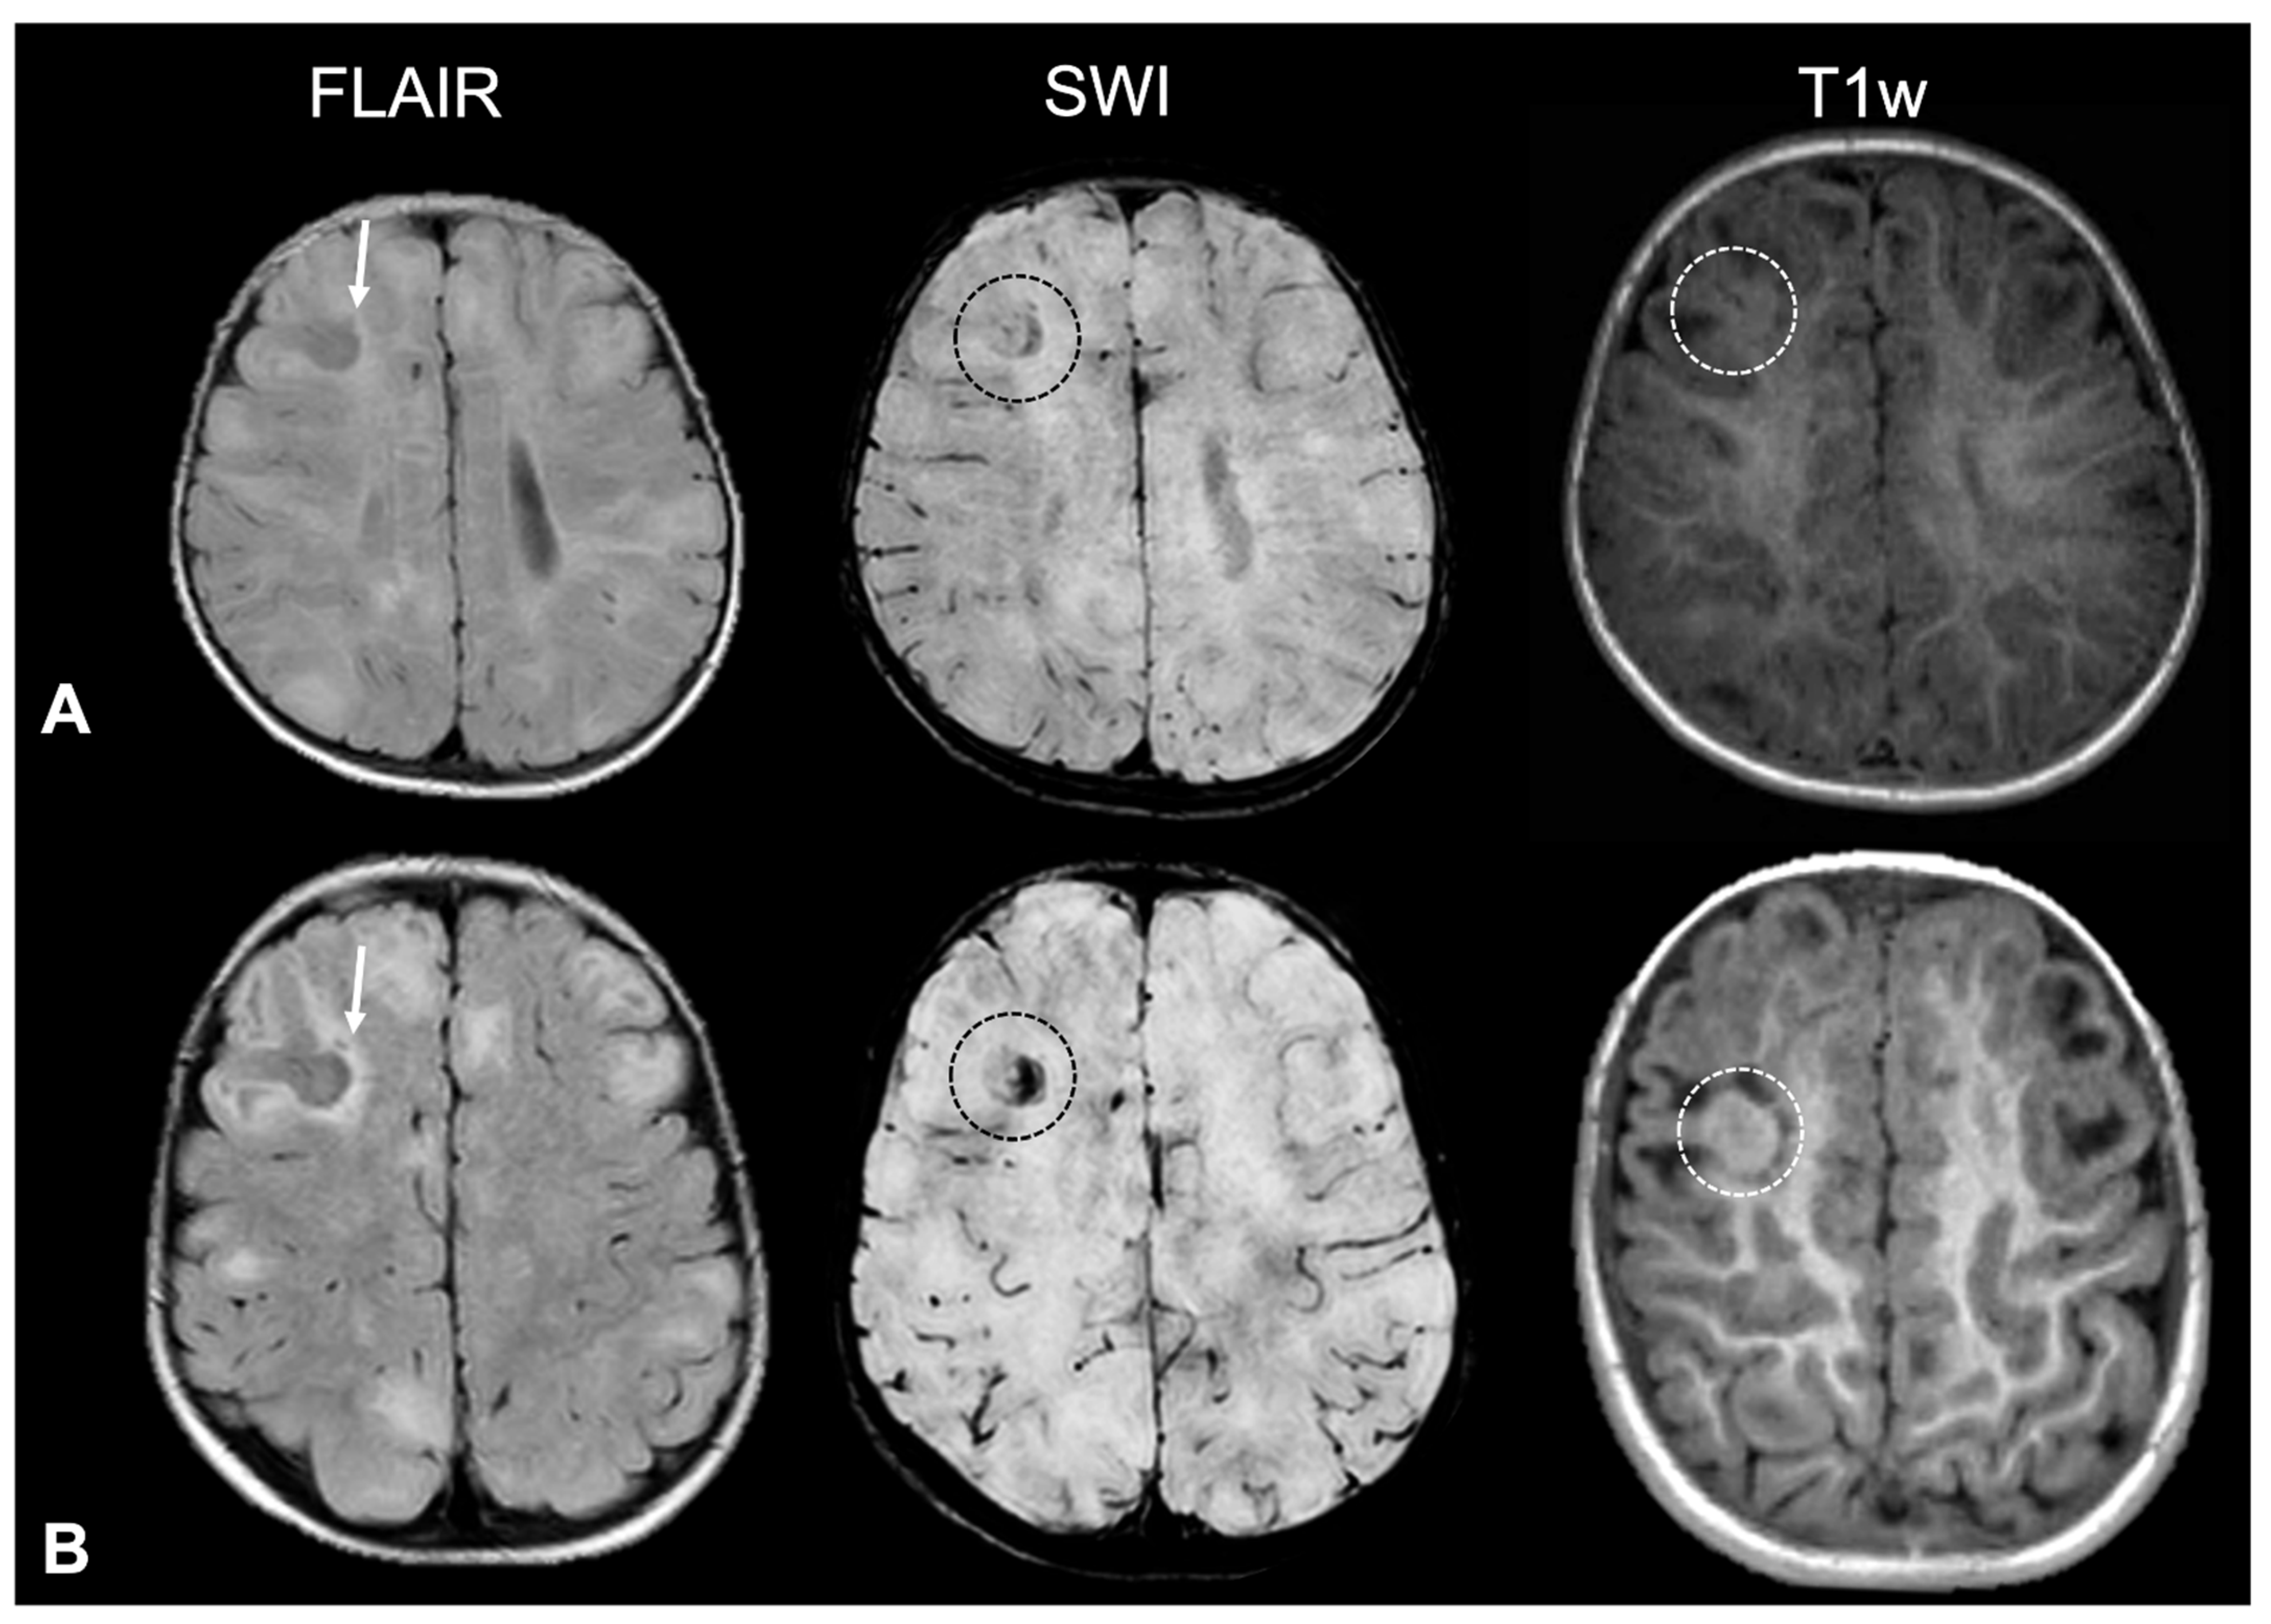

- Tuber A (corresponding to former tuber A in the classification by Gallagher et al., 2010 [27]): isointense on volumetric T1-weighted images and subtly hyperintense on T2-weighted images, with no mass effect, no distortion of the gyral folding pattern, and no calcifications on SWI.

- Tuber B (corresponding to former tuber B in the classification by Gallagher et al., 2010 [27]): hypointense on volumetric T1-weighted images and homogeneously hyperintense on T2-weighted images, with no well-defined borders, minimal mass effect, slight disruption of the gyral pattern, and no calcifications on SWI.

- Tuber C: hypointense on volumetric T1-weighted images and homogeneously hyperintense on T2-weighted images with inner calcifications on SWI, further divided into the following:

- Tuber D: hypointense on volumetric T1-weighted images and homogeneously hyperintense on T2-weighted images with a central cystic area of vacuolization, regardless of the presence of associate calcification(s).

- Tuber A: isointense on volumetric T1-weighted images and subtly hyperintense on T2-weighted images, with no mass effect, no distortion of the gyral folding pattern, and no calcifications on SWI

- Tuber B: hypointense on volumetric T1-weighted images and homogeneously hyperintense on T2-weighted images, with no well-defined borders, minimal mass effect, slight disruption of the gyral pattern, and no calcifications on SWI

- Tuber C1: with subtle, non-confluent, pinpoint-like calcifications on SWI (micro-calcified)

- Tuber C2: with large, confluent, linear or curvilinear calcifications on SWI (macro-calcified)

- Tuber D: hypointense on volumetric T1-weighted images and homogeneously hyperintense on T2-weighted images, with a central cystic area of vacuolization, regardless of associated calcification(s).